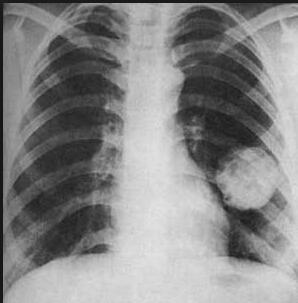

肺部鳞状细胞癌是肺癌中最常见的类型之一,占所有肺癌病例的约40%,近年来,随着医学研究的不断深入,肺部鳞状肿瘤的治疗方案取得了显著进展,许多患者能够获得长期生存甚至治愈的机会,本文将探讨肺部鳞状肿瘤的治愈可能性、影响因素及最新治疗方法。

肺部鳞状细胞癌起源于支气管黏膜上皮细胞,通常发生在吸烟者中,早期症状不明显,多数患者在确诊时已处于晚期,这大大降低了治愈率。